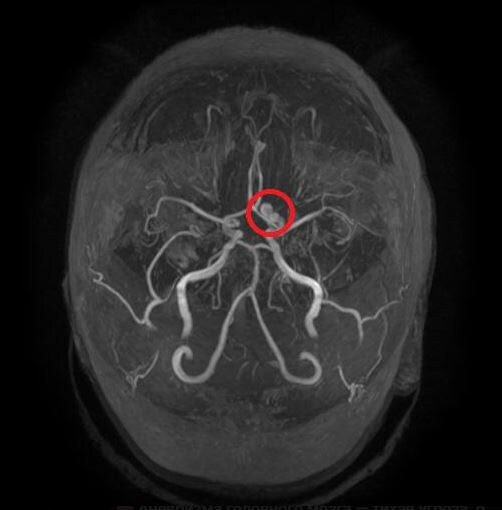

Аневризма головного мозга на МРТ

МР-ангиография — безболезненный метод, который позволяет «увидеть» сосуды мозга.